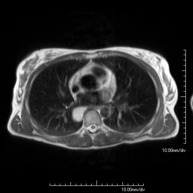

- RM Tórax

Prueba diagnóstica no invasiva que consiste en la obtención de imágenes de alta definición anatómica del tórax mediante el empleo de un campo electromagnético y ondas de radio (con un emisor y un receptor). No utiliza radiación ionizante. Está indicada en aquellas lesiones pulmonares en las que debe descartarse si existe infiltración del mediastino o de la pared torácica, para diferenciar si una lesión torácica es sólida o quística, etc. En ocasiones se deberá emplear contraste paramagnético (Gadolinio) para completar el estudio.